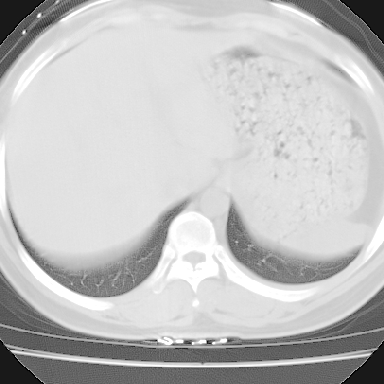

右肺多发小结节影,边界清楚,符合转移瘤的特点;2、左下肺偏心性空洞影,右侧乳腺内高密度影,需要查体除外右侧乳腺肿瘤;3、腋窝淋巴结肿大,考虑转移。

支持癌性空洞:壁厚,无液平,内壁不规则,外壁呈分叶状,较大,偏心性,壁结节,胸膜凹陷,转移灶。

左下肺肿块影,内可以见小泡征,并见厚壁空洞形成,洞内缘凹凸不平,可见壁结节。靠近胸膜侧可见胸膜凹陷征。左侧胸腔内可见少量低密度积液影。双肺可见多发性小结节影。

考虑:左下肺癌性空洞伴两肺转移